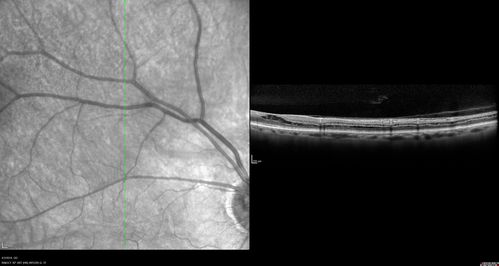

Stellate Non-heredtiary Idiopathic Foveomacular Retinoschisis (SNIFR)

77 year old man who is healthy and 6'6" tall with 20/40 vision and no complaints. OCT shows diffuse retinoschisis.